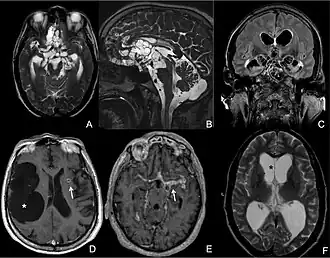

| Magnetic resonance image of a patient with neurocysticercosis demonstrating multiple cysticerci within the brain[1] | |

CT scans and magnetic resonance imaging (MRI) give objective information about the number and pattern of lesions, the stage of healing, and how the immune system is responding to the parasites.[19] MRIs are better for evaluating different spatial planes and provides clearer images, which helps in identifying small lesions at the back of the brain or near the skull that may be missed on CT scans. CT scans are more sensitive at detecting calcium buildup in the brain due to its ability detect calcifications in the brain.[30]

Live vesicular cysts are small, round lesions with little swelling around them and do not need contrast for imaging. The tapeworm head (scolex) usually appears as an asymmetric nodule inside the cysts. Multiple live cysts with these heads corroborate the diagnosis. Once the cysts begin to break down (colloid cysts), their borders become unclear, they are surrounded by swelling and exhibit significant ring or nodular contrast enhancement. Calcified cysticerci are shown on CT scans as non-enhancing hyperdense nodules without swelling.[20]